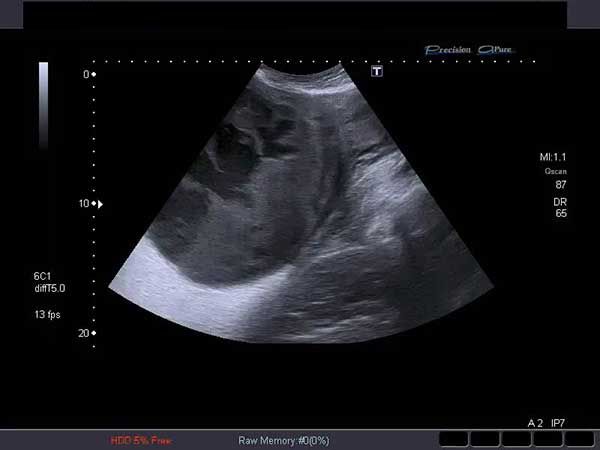

When a 35-year-old woman presented for her first ultrasound at 30 weeks’ gestation, the images revealed a very rare condition. Can you identify it?